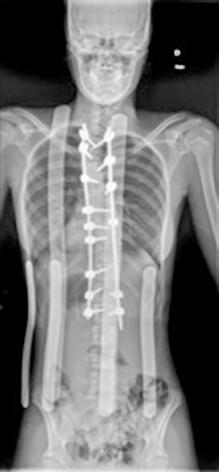

OBSTRUCCIÓN INTESTINAL ALTA TRAS CIRUGÍA DE CORRECCIÓN DE ESCOLIOSIS EN UNA PACIENTE ADOLESCENTE: UNA PRESENTACIÓN AGUDA DEL SÍNDROME DE LA ARTERIA MESENTÉRICA SUPERIOR.

Raquel Ros Briones.

Cirugía Pediátrica. Hospital Universitario de Navarra (HUN).

Arredondo Montero J., Moreno Alfonso J.C., Ugarte Mugarza L.C., Pérez Martínez A. (supervisión clínica).